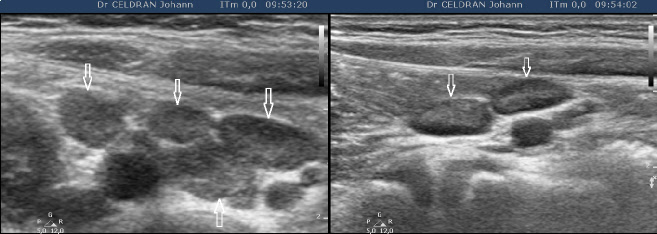

Celle d’une adénite mésentérique chez une petite fille âgée de 6 ans présentant une douleur franche de la fosse iliaque droite fébrile. Les images sont prises avec une sonde linéaire (haute fréquence) en fosse iliaque droite.

On retient finalement comme critères diagnostique d’adénite mésentérique de l’enfant :

- au moins 3 ganglions de petit axe supérieur 8mm

- un tableau clinique évocateur

- l’absence de signes échographiques orientant vers un caractère secondaire de l’adénolymphite (appendicite, iléite, colite infectieuse…)